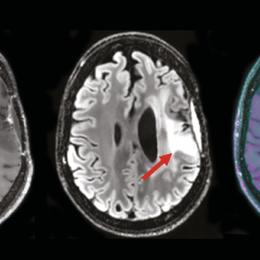

Toxoplasmose cérébrale révélant une infection par le VIH

Un homme âgé de 51 ans, sans antécédents particuliers, a depuis deux semaines une hémiplégie droite et une dysarthrie...

edd7c61a-89cc-4c80-9568-3cc9dfa58b38.jpg